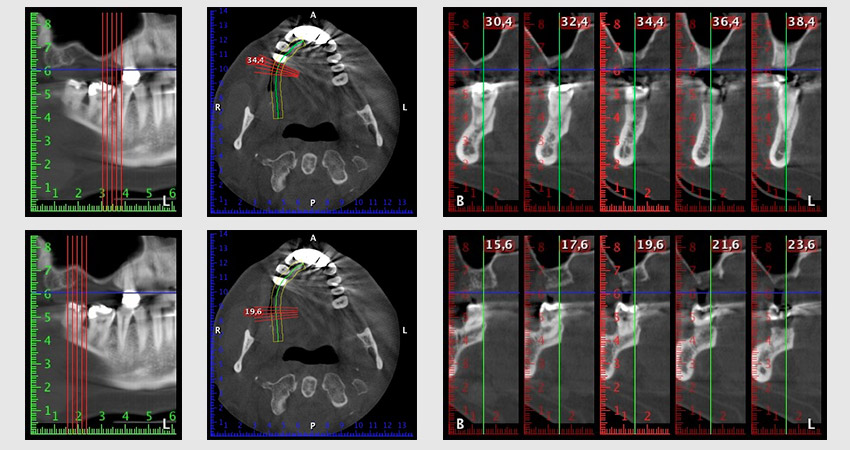

За да ограничим аугментацията до зона 14, след консултация с пациентката, е планирано поставяне на имплант в зона 16, наклонен по посока на челюстта (Фиг. 8).

Този метод изисква винтово фиксиране за финално възстановяване. Необходим е ангулиран абатмънт (например 35°) така, че винтът да бъде перпендикулярен на оклузалната равнина, която позволява мостът да бъде захванат оклузално.

Снимка 8: DVT с план за ъгъла на поставяне на имплант 16